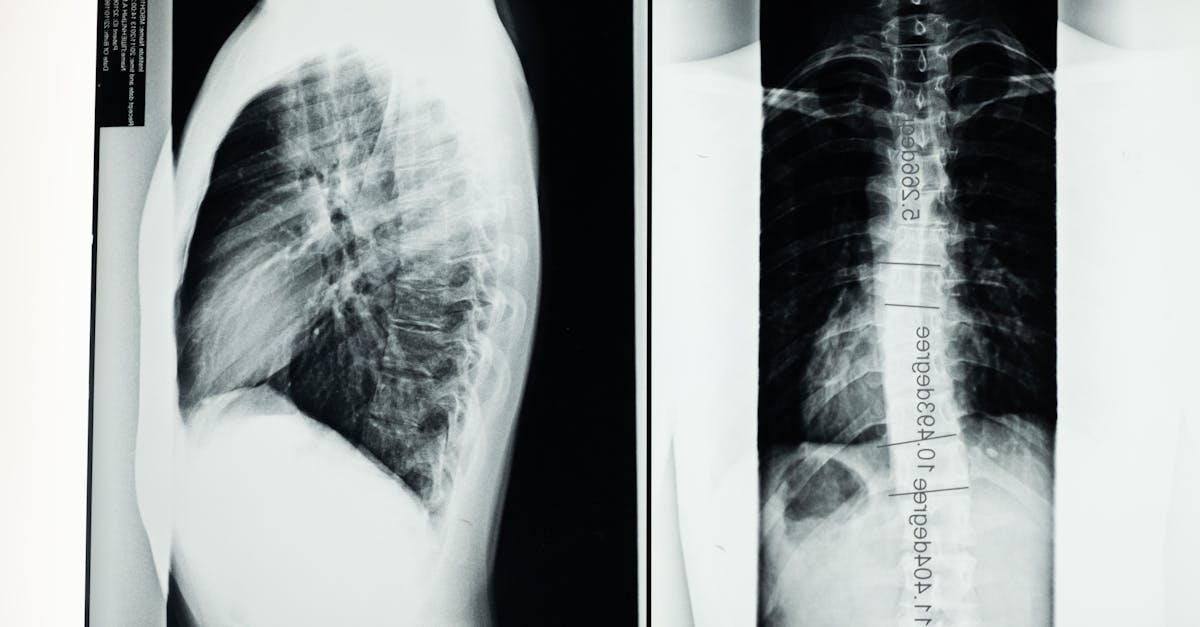

Avant d’entamer un traitement, une évaluation approfondie est nécessaire. Le professionnel de santé effectue généralement des examens physiques et peut recommander des examens complémentaires comme des radiographies. Cette étape permet d’identifier les niveaux de la colonne vertébrale touchés et d’élaborer un plan de traitement physique adapté.

Avant d’élaborer un protocole de traitement, une évaluation approfondie de l’état médical global et des spécificités de la sténose est essentielle. Un examen physique complet, accompagné d’imageries adaptées comme des radiographies, des IRM ou des CT scans, permettra de déterminer l’étendue et la localisation de la sténose ainsi que l’impact sur la moelle épinière et les nerfs environnants.

| Imagerie médicale | Utilisation de radiographies, IRM ou TDM pour visualiser l’étendue de la sténose. |